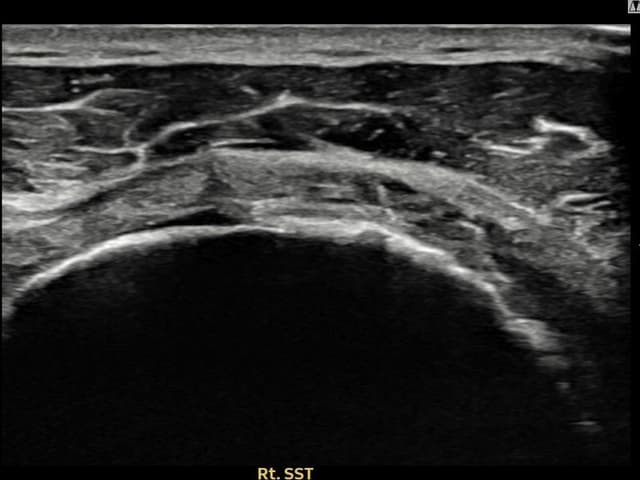

[経過期間: 24.04.26~24.07.05]

[縫縮術] 超音波検査にて右 棘上筋腱 관절면측 광범위 部分断裂(16mm × 5mm (腱厚の約75%欠損))を確認。縫縮術施行後、腱の連続性が回復し、日常生活に復帰されました。